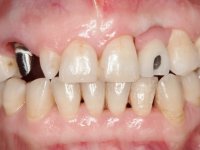

The patient complained that she had a front tooth shaking, did not like the "dark canine" and also "wanted to close the spaces between the teeth”. After 8 years of initial treatment, what motivated a second treatment phase was that the "two front teeth are ugly."

Female patient, 47 years old non-smoker. Tooth 1.3 with endodontic treatment and a cast post and core, rehabilitated with a provisional crown. The two upper lateral incisors are conoid and of small dimension. Tooth 2.2 presents mobility, in agreement with a significant bone reabsorption between teeth 2.1 and 2.3. The two central incisors are separated by a 3 mm diastema and tooth 2.3 presents a crossed occlusion with the opposing tooth. There is also an absence of some posterior teeth and reasonable oral hygiene. In the second intervention performed 8 years later, it was verified that the upper central incisors were chromatically darker and had a longitudinal groove in the enamel which, being pigmented, aesthetically compromised the smile. The work performed in the first phase of the treatment was competent, aesthetically and functionally. Finally, one year after the last intervention, the patient complained of a fracture on the veneer placed on tooth 2.1, probably as a result of being in contact with the abutment of the implant. The rigidity of implant ankylosis may have been the cause of this fracture. I have observed other instances of this type of fracture in identical clinical situations. The veneer of tooth 1.2 was aesthetically compromised and the dental structure itself had small caries and, therefore, its replacement would be recommended.